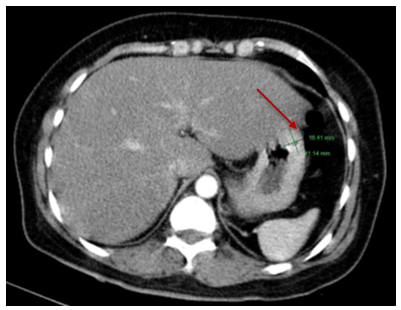

Chụp cắt lớp vi tính ổ bụng có tiêm thuốc: Vị trí bờ cong lớn dạ dày có nốt kích thước 21x15mm, phát triển ra ngoài dạ dày, không phá hủy lớp niêm mạc dạ dày, bờ đều ranh giới rõ, ngấm thuốc tương đối đồng nhất sau tiêm, không thấy hạch to lân cận.

Hình 4. Hình ảnh chụp CT ổ bụng: Nốt ở bờ cong lớn dạ dày kích thước khoảng 21x16 mm (vị trí mũi tên đỏ)